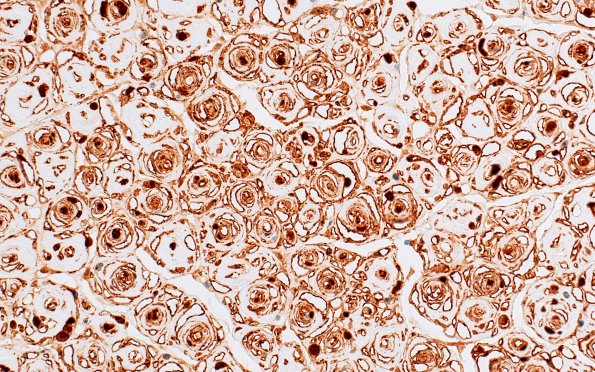

8C5 CIDP (Case 8) Roots S100 40X 2

Higher magnification images show numerous onion bulbs. (S100 IHC)